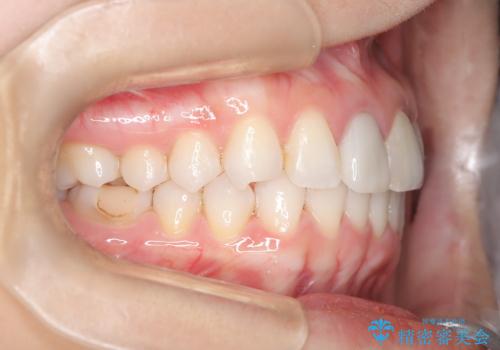

- 前歯のガタつき、変色を主訴に来院された患者様です。術前診査のCT撮影にて、変色した前歯の根の先に病巣があることが判明しました。そこで、マウスピースによる矯正治療と、前歯の根管治療、かぶせ物のやり直し治療を並行して行いました。